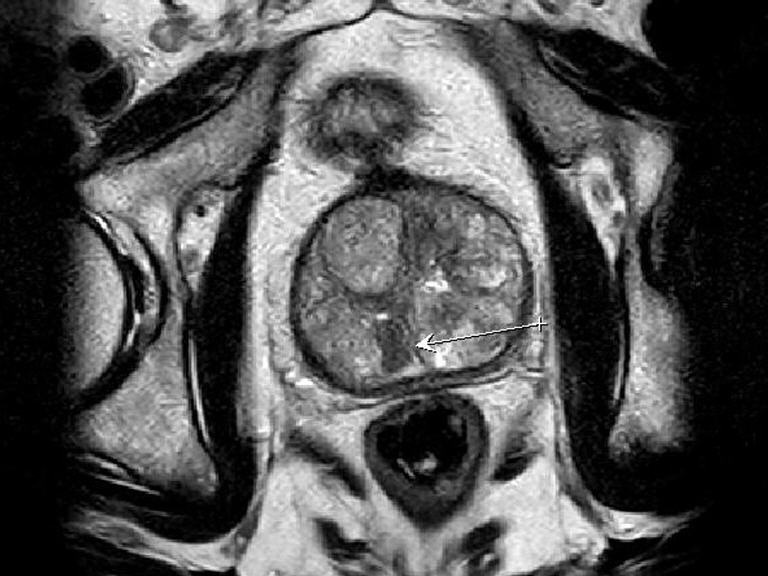

Prostata-MRT

Ein erhöhter PSA-Wert oder der Verdacht auf Prostatakrebs kann viele Fragen aufwerfen. Mit dem Prostata-MRT bieten wir Ihnen eine moderne, nicht-invasive Untersuchung, die höchste Präzision und Sicherheit bei der Diagnose gewährleistet. Durch die detaillierte Bildgebung können selbst kleinste Tumore frühzeitig erkannt und gezielte Biopsien durchgeführt werden.